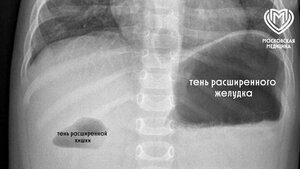

Мальчика, испытывавшего острую боль в подреберье, экстренно госпитализировали из-за подозрения на аппендицит. По итогам обследования специалисты медучреждения выяснили, что причиной дискомфорта стала 5-сантиметровая швейная игла. Инородный предмет застрял в поперечной ободочной кишке и проткнул ее.

В ходе операции по извлечению объекта врачи обнаружили небольшое отверстие размером в 2 миллиметра, располагавшееся в месте стояния иглы. Металлический предмет выступал ушком в просвет брюшной полости – брыжеечной части кишки, где более толстая стенка.

По словам детского хирурга отделения экстренной хирургической помощи Максима Сергиенко, благодаря своевременному обнаружению иглы и ее малым габаритам герметичность кишки была сохранена. Тем самым перфорация зажила самостоятельно без ушивания.